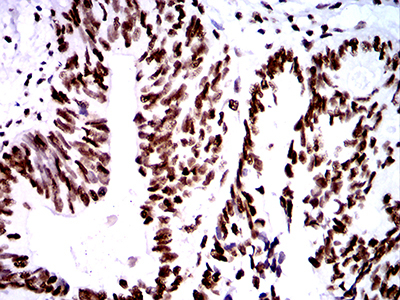

Supportive validation

- Submitted by

- LSBio (provider)

- Enhanced method

- Genetic validation

- Main image

- Experimental details

- Immunohistochemical analysis of paraffin-embedded ovarian cancer tissues using ZFP91 mouse mAb with DAB staining.